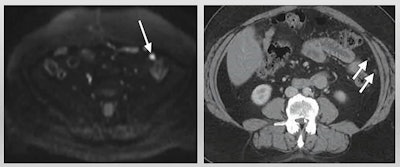

"MRI is certainly much more definitive in showing a solid mural nodule with post-contrast enhancement more consistent with an ovarian mass," she said. "The value of MRI is to be able to look at that solid component in much more detail."

Sahdev cited previous research touting MRI over CT. The most recent research was a 92-patient study published in 2020 in the European Journal of Radiology, which showed that diffusion-weighted imaging (DWI) MR had overall higher accuracy than CT in evaluating all sites. DWI also performed "significantly better" than CT for involvement of mesentery, periaortic lymph nodes, and bowel serosa.

Another study Sahdev cited was published in 2016 in the British Journal of Radiology. The authors found that diffusion-weighted MRI had higher overall sensitivity than CT, 98% to 83%. They also found that MRI detected more surgically critical sites, such as smooth muscle actin activity, small- and large-bowel serosa, and mesenteric root, among others. However, the researchers did not validate their disease sites with histology or surgical findings, Sahdev said.

Still, Sahdev said MRI has advantages via increased tissue contrast and increased conspicuity for small lesions through diffusion-weighted MR. It also shows direct disease response with alterations in apparent diffusion coefficient measurements.